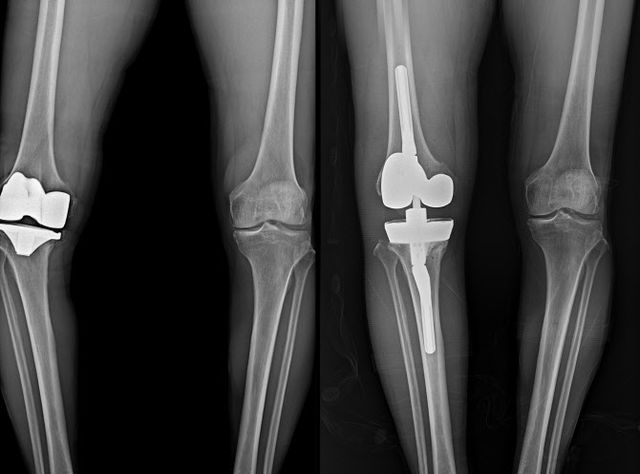

그러나 평균 수명 증가에 따르는 인공 관절 마모뿐 아니라 부정정렬, 인공관절 불안정성, 해리, 감염 등으로 인해 재수술이 필요한 경우는 여전히 존재하며, 국내외 연구에 따르면 전체 인공관절 수술의 약 5~10%가 재치환이 필요한 것으로 알려져 있다.

문제는 재수술이 첫 수술보다 훨씬 복잡하고 고난도의 기술을 요구한다는 점이다. 연세사랑병원의 자체 통계에 따르면 지난 10년간 무릎 인공관절 재수술을 받은 환자 833명 중 58%인 483명이 70대 이상의 고령이었다. 고령 환자의 경우 동반된 기저질환을 고려해야 하기 때문에 수술 전 환자 평가를 위한 내과 전문의와의 협진이 필수적이다.

연세사랑병원 인공관절재수술센터는 1천례에 달하는 풍부한 재수술 경험을 기반으로 수술의 안정성과 효율성을 높이고 있다. 병원은 앞서 설명한 재수술의 까다로움과 어려움을 줄이기 위해 정형외과, 내과, 영상의학과, 통증의학과의 협진 시스템을 구축했다. 이를 통해 ▲정확한 원인 진단 ▲증상과 상태에 맞는 수술 및 치료 ▲수술 후 통증 관리 ▲ 재활까지 환자 개개인에 맞는 치료를 진행한다.

의료진의 임상경험과 잘 구축된 시스템을 바탕으로 수술시간도 줄어들었다. 일반적으로 재수술은 첫 수술에 비해 두 배 이상의 시간이 소요되는 것으로 알려져 있다. 그러나 연세사랑병원 재수술센터의 평균 수술 시간은 1시간 10~20분 가량으로 첫 수술 평균 40~50분의 소요시간에 비해 불과 30분 정도만 더 소요된다.